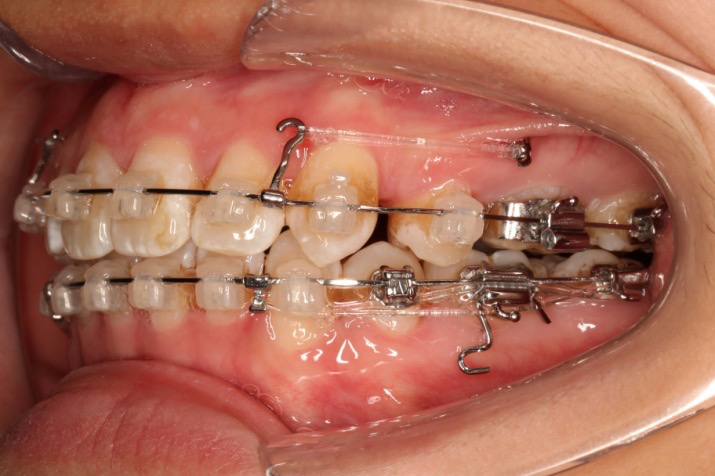

2017.07.25

2017.07.25  上前牙加颈部弹力线

2017.10.07

2017.10.07  继续关间隙,下颌使用水平关间隙

下颌磨牙通过powerarm直立效果明显,下颌整平效果明显

2017.12.15

2017.12.15  继续关间隙

2018.03.01上TPA加17、27颚侧牵引钩,压低17、27颚尖下颌43、32重粘,下颌0.016*25niti

2018.04.20  间隙基本关闭,上颌重新整平,精调

2018.5.25  (19个月)拆TPA,16、26粘tube 上颌0.14*25cu-niti  下颌0.018*25niti2018.7.23  上颌 0.017*25TMA,下颌0.017*25ss43压低曲,双侧后牙垂直牵引

2018.09.29  15、43、16、17、11、21重粘,上0.016*25cu-niti 下0.018niti 上连扎